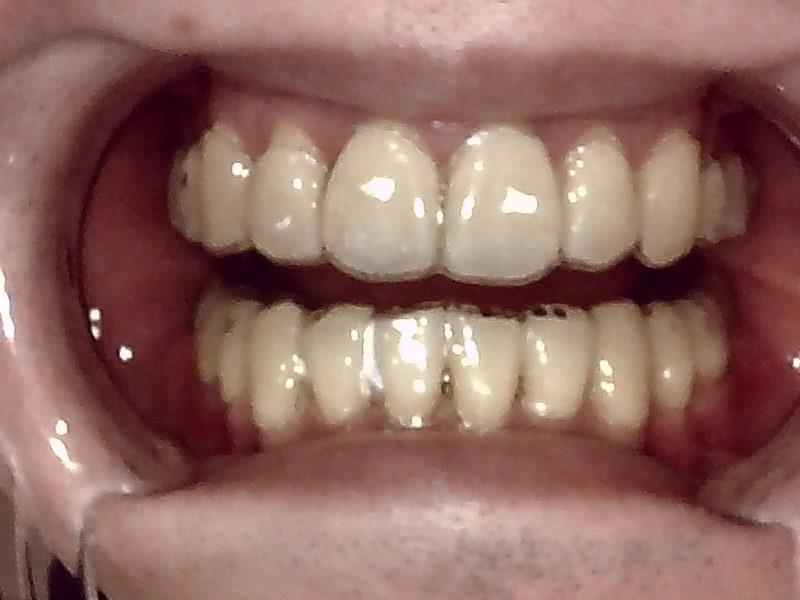

30代後半の女性の親知らずの症例になります。

レントゲン写真の状態を御覧ください。

術前パノラマレントゲン写真

部位:右上8番骨性完全埋伏歯

部位:右下8番骨性完全埋伏歯

部位:左上8番骨性完全埋伏歯

部位:左下8番骨性完全埋伏歯